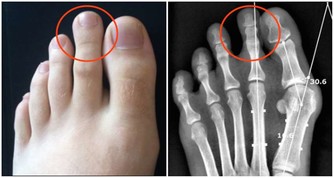

*****3、異常三:腳腫*****

血管堵塞,血液的流通受阻,進而就會造成腳經常水腫。